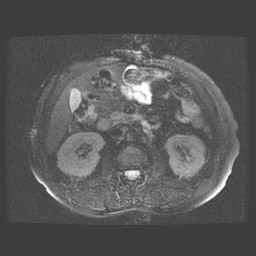

Abdomen